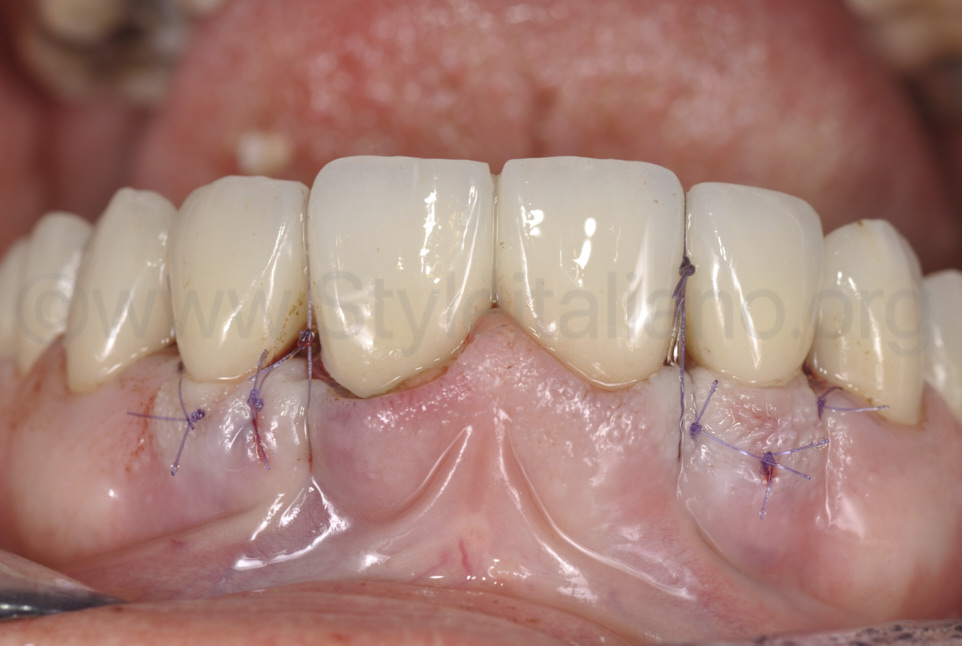

Фото 12.

Після фіксації керамічної реставрації, було накладено підвісні шви, щоб вони підтягували сполучнотканинний трансплантат та поверхневу оболонку в напрямку коронки.